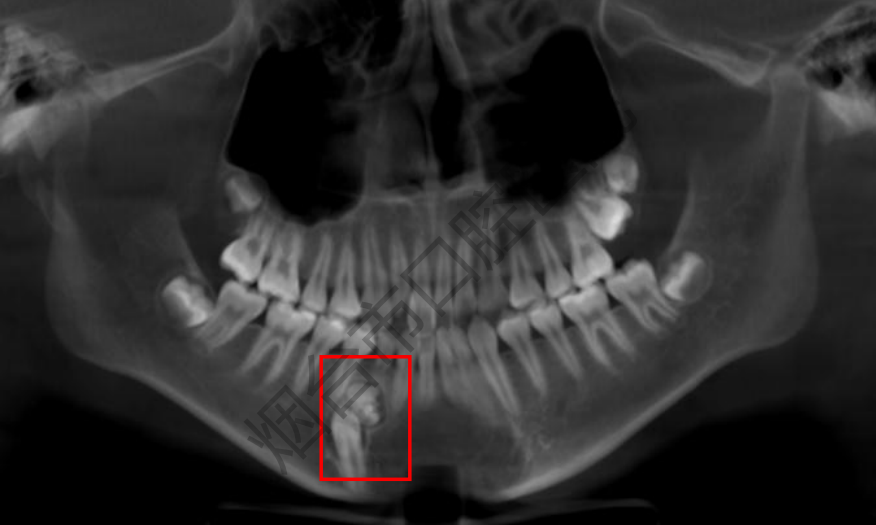

精准诊治:一张牙片,化解颌骨“隐形危机”

2025-12-12 16:18:15 今日推荐 来源:烟台市口腔医院